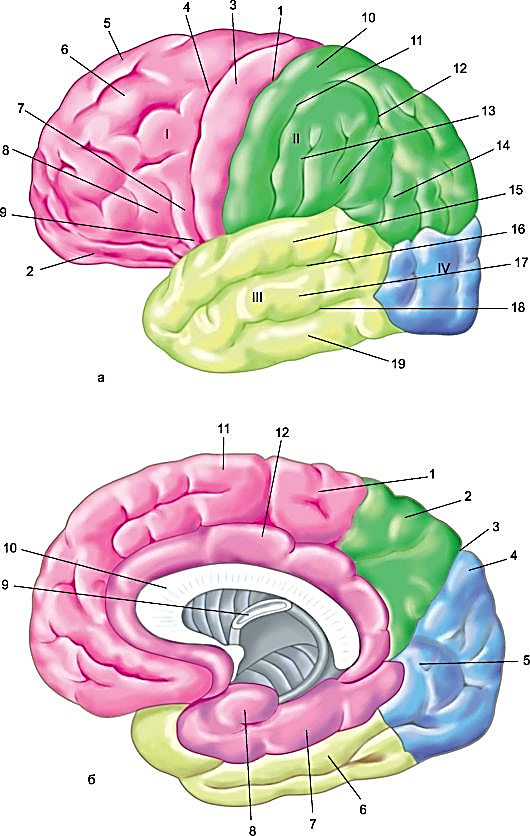

Анатомические снимки верхнелатеральной поверхности головного мозга